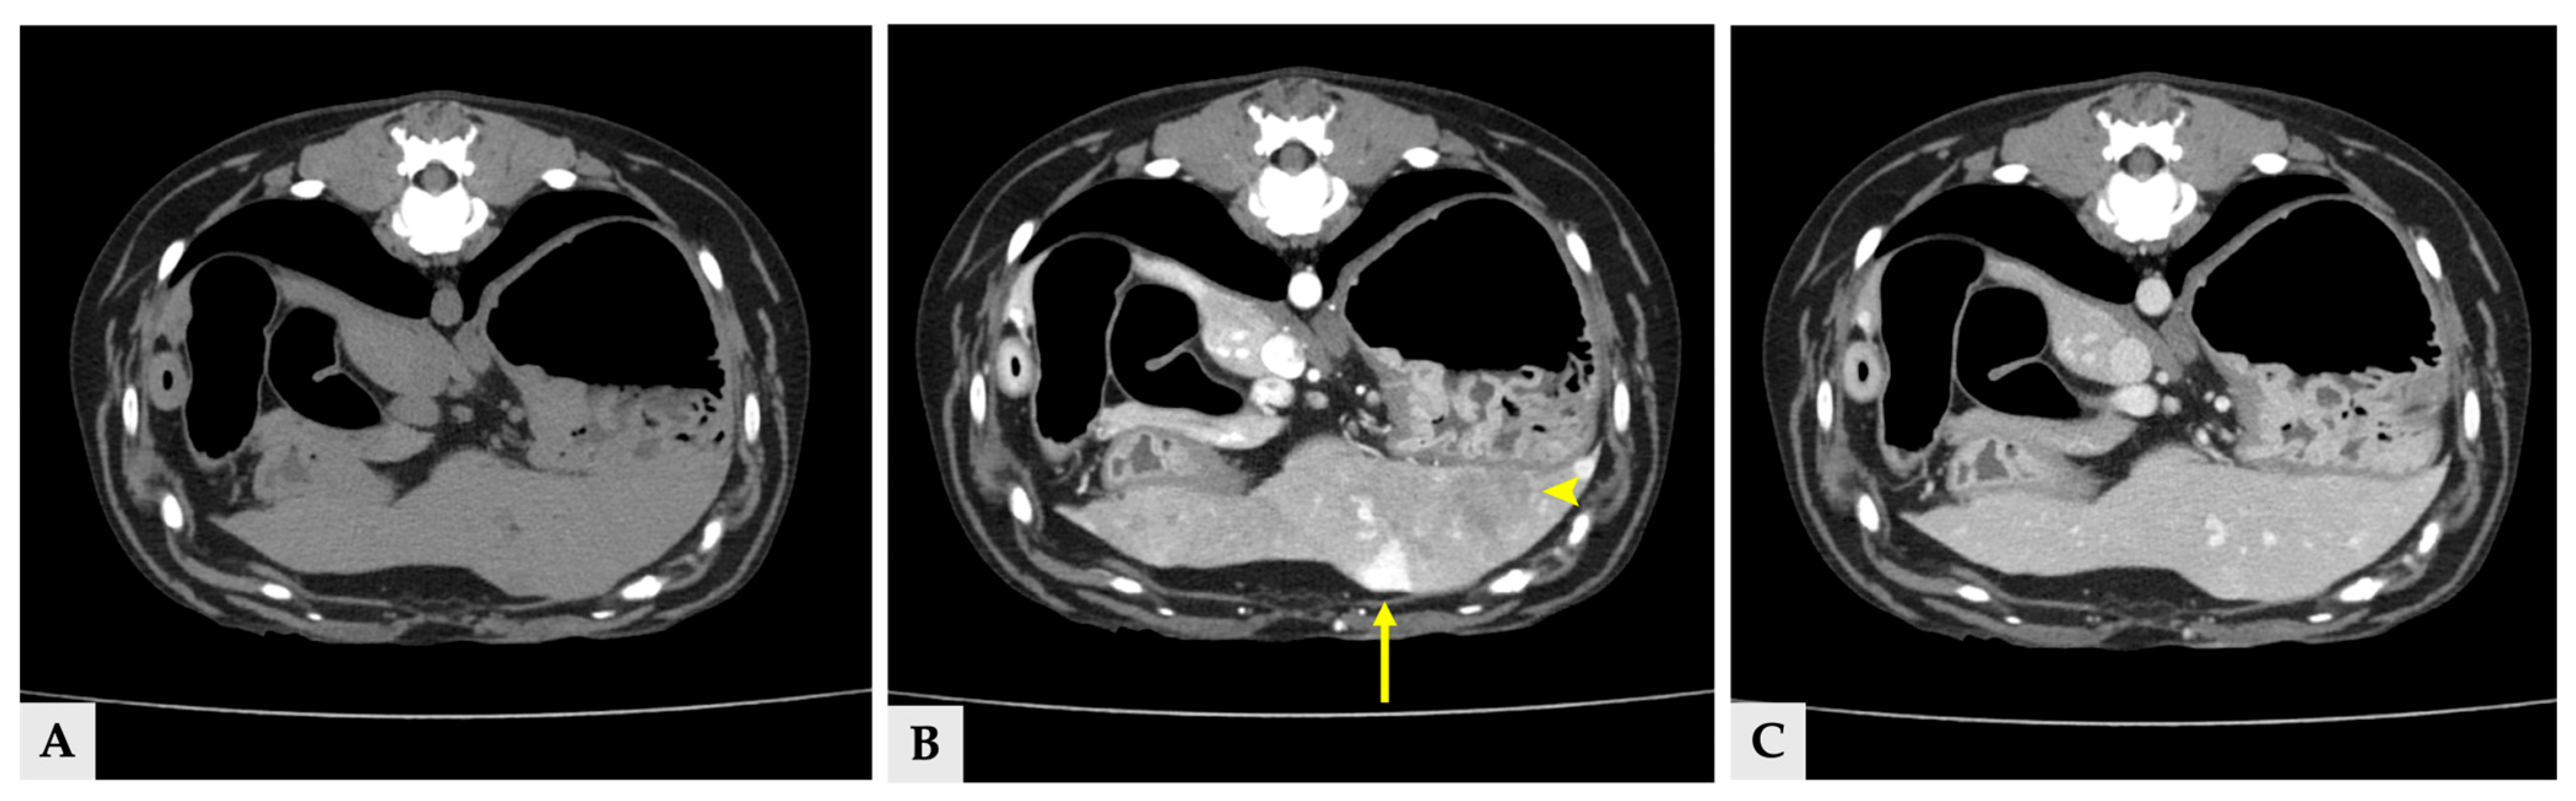

Multiple hyper- and hypoattenuating hepatic nodules were scattered throughout the liver parenchyma (maximum size 11.4 mm × 11.9 mm × 10.8 mm) (Figure 3), and numerous small splenic nodules exhibiting on pre-contrast and portal phase were also observed (Figure 4). Additionally, a soft-tissue mass was detected at the esophagogastric junction. Cervical ultrasonography revealed three distinct, heterogeneous right thyroid masses, with the largest mass demonstrating prominent vascularity on Doppler evaluation (Figure 5).

Figure 3.

Transverse view of the CT images of several hepatic nodules at the same anatomical level. (A) Pre-contrast image showing a liver nodule with attenuation similar to the surrounding hepatic parenchyma. (B) Portal phase image at the same level demonstrating heterogeneous hyperattenuation (arrow) and hypoattenuation (arrowhead). (C) Delayed phase image at the corresponding level, in which the nodules show attenuation similar to the surrounding hepatic parenchyma. The yellow arrows in all three images indicate the same liver nodule (11.4 mm × 11.9 mm × 10.8 mm).

Figure 4.

Transverse CT images of splenic nodules at the same anatomical level. (A) Pre-contrast image showing splenic nodules that are isoattenuated relative to the surrounding splenic parenchyma. (B) Portal phase image at the same level demonstrating hyperattenuated splenic nodules (arrows). (C) Delayed phase image at the corresponding level, in which the splenic nodules show attenuation similar to or slightly higher than the surrounding splenic parenchyma.